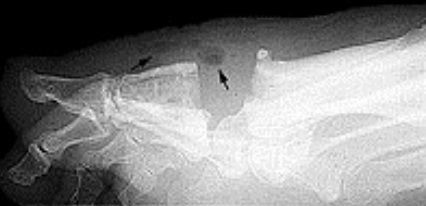

What disease is this? What does the arrow indicate? | Rheumatoid arthritis. Arrow = Bone erosion secondary to inflammation of retrocalcaneal bursa. |